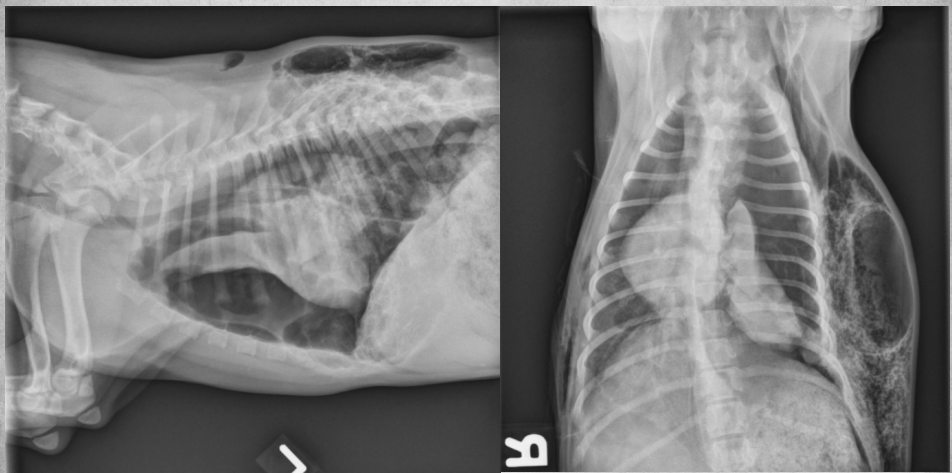

● 2 yo Labrador

● Ingested laundry detergent the day

before

black hole is bifurcation

air bronchograms visible -> alveolar pattern

lobar sign in lower VD image

aspiration pneumonia -> chemical burn in the lungs secondary to laundry detergent aspiration